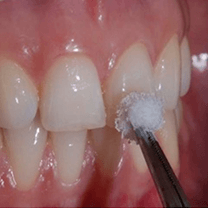

Vital Whitening

In this method a gel containing Hydrogen Peroxide is applied onto the teeth, while covering the gums so that they are not harmed, followed by a special light which activates the gel to start the bleaching. A hassle free process, and requires mostly one to two visits for 30-40 min each (depends highly on the patient) to the dentist.